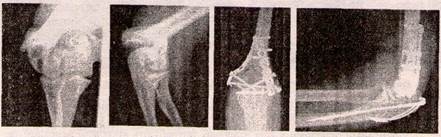

Для остеосинтезу Т- і У-подібних переломів виростка плечової кістки використовують методики Кемпбелла, Лангенбека. При цьому для співстав-лення відламків часто виконують остеотомію ліктьового відростка з наступним його остеосинтЛом гвинтом (рис. 15).

Рисунок 15 - Перелом виростків плечової кістки до та після операції

У випадку Т-подібного перелому, де горизонтальна площина зламу проходить вище виростка, у дорослих для остеосинтезу використовують реконструктивні пластини по медіальному і латеральному краю дистального метаепіфізу плечової кістки (рис. 16).

Рисунок 16 - Т-подібний перелом виростків плечової кістки до та після операції